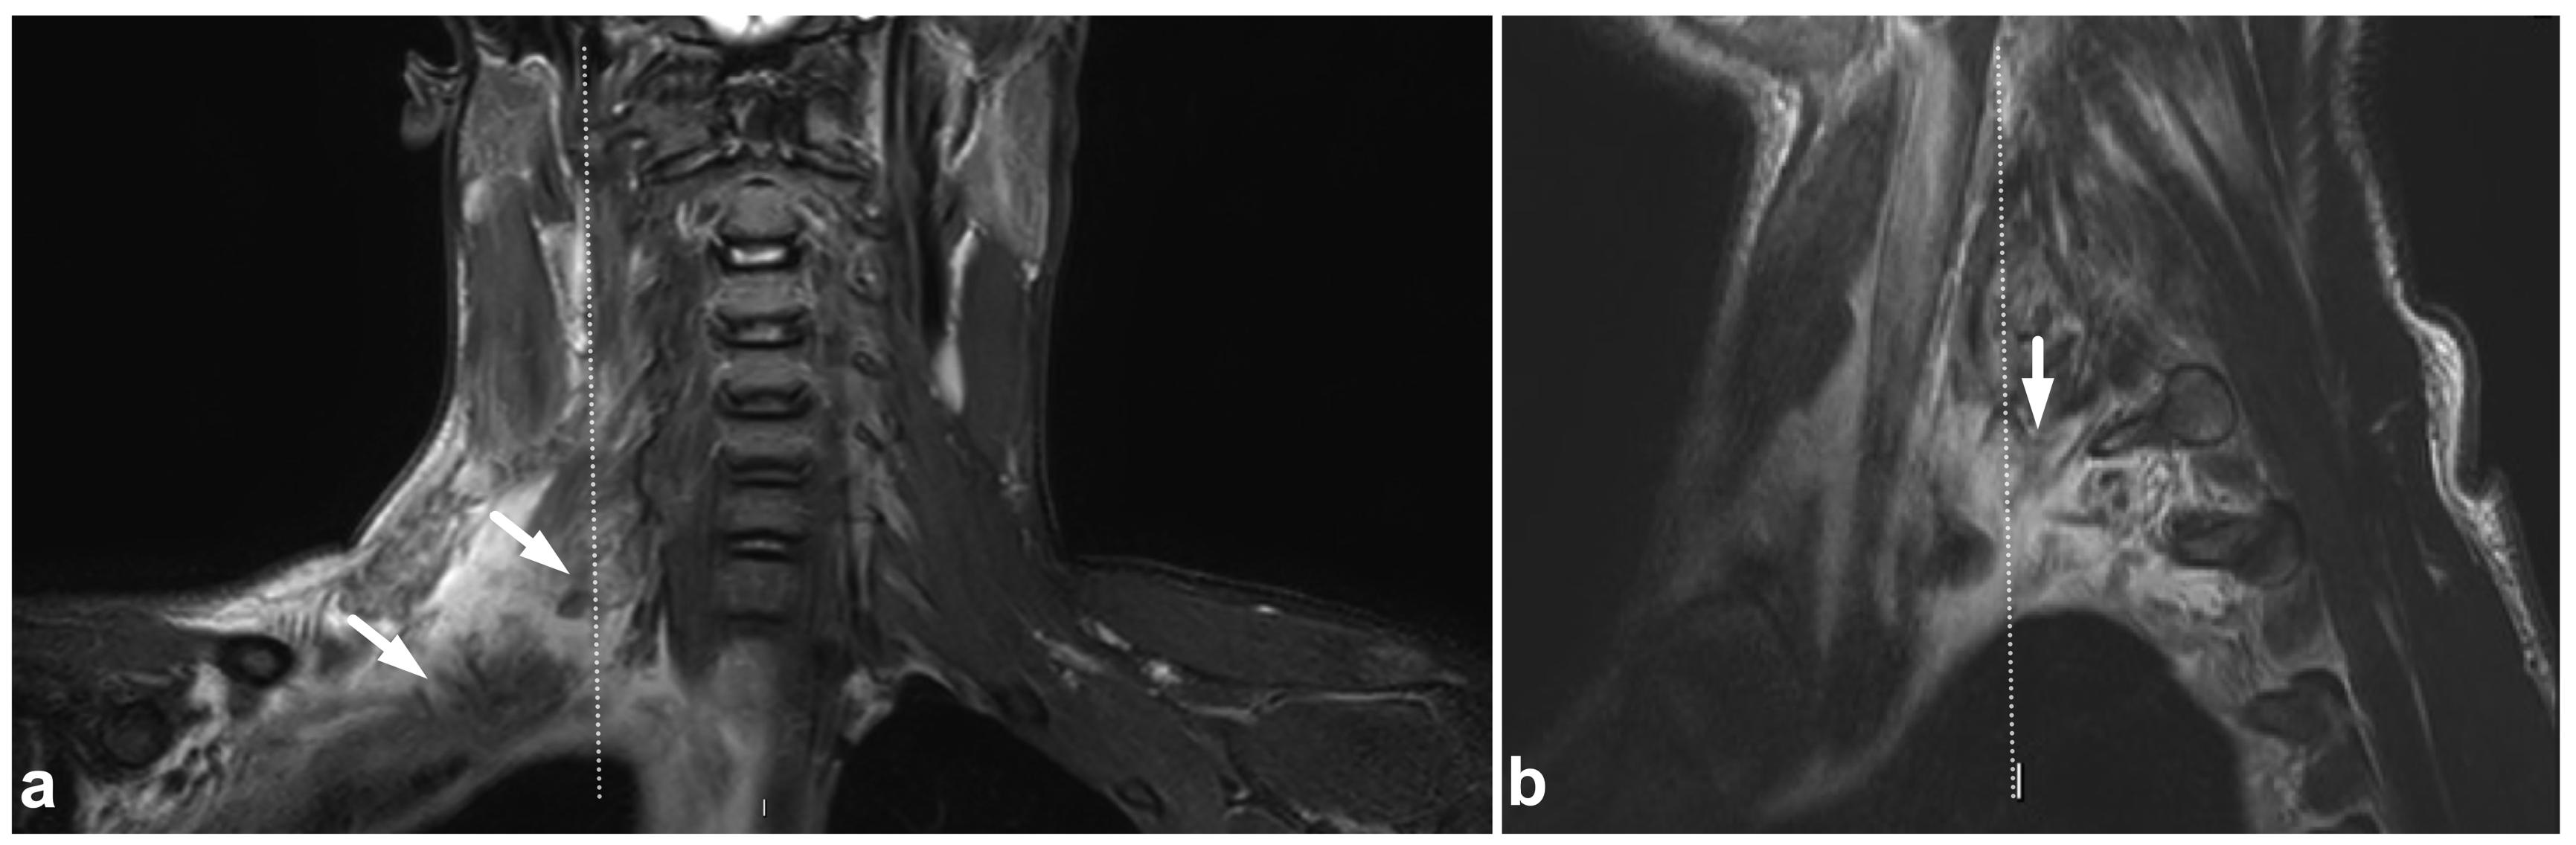

Figure 13.

(a) Coronal STIR. (b) Sagittal T2-weighted. The dotted line in the image (a) represents the plane of the sagittal image (b) and vice versa. A 13-year-old male after a moped accident. MRI demonstrates a muscle injury and significant edema at the brachial plexus region (arrows). This emergency imaging was not definitive in assessing the extent of the injury. However, extending the cervical imaging to examine the plexus region tentatively helped to confirm the clinical suspicion of upper extremity paralysis being caused by a brachial plexus injury and not a central nervous system injury.